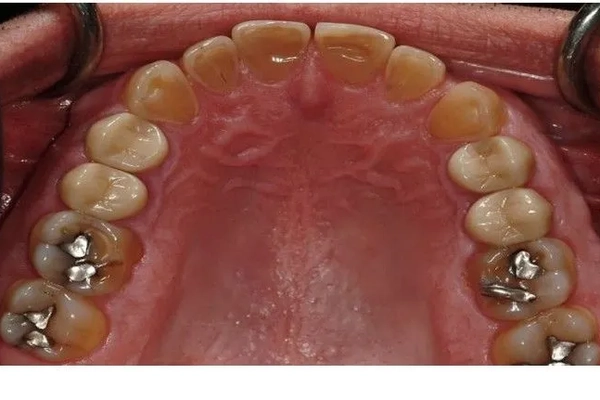

Before

Mercury-Free Dentistry Before and Afters at Suite Dental